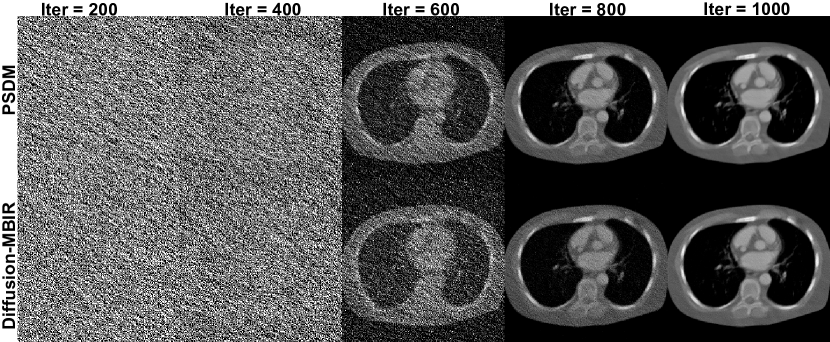

Refer to caption

Figure 8: Reconstructed images of the PSDM and Diffusion-MBIR with respect to different reverse diffusion steps on 120 views. The display window is [540540-540 100010001000] HU.

Figure. 7 presents a comparative analysis of the reconstruction results with and without the TV term. These quantitative metrics (SSIM and the PSNR) indicate that the TV term can improve the perceptual quality and the fidelity of the reconstructed images. Visually, results with the TV term exhibit less noise and more consistent structural integrity compared to those without the TV prior. Figure. 8 illustrates the performance comparison between PSDM and Diffusion-MBIR with respect to numbers of reverse diffusion steps. It is observed that PSDM demonstrates faster convergence relative to Diffusion-MBIR. Specifically, in the iterations ranging from 600 to 800, Diffusion-MBIR exhibits higher noise levels compared to PSDM. Figure 9 provides a quantitative comparison of the performance with and without the Fourier fusion module. It is observed that between 400-800 reverse steps, the PSDM (presumably a metric being compared) with the Fourier fusion module outperforms the one without it. Ultimately, both the PSNR and SSIM metrics show a slight improvement when the Fourier fusion module is utilized, highlighting its benefits.